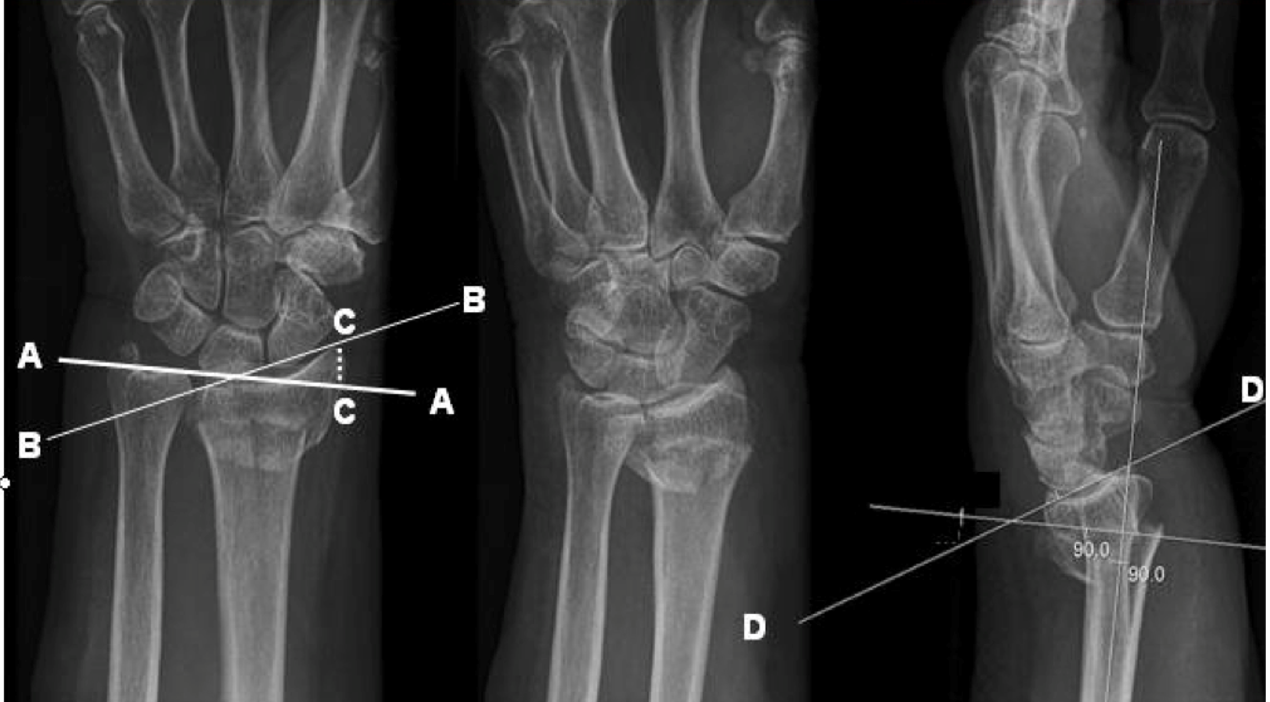

Radial Fracture Reduction Parameters

A

Acceptable parameters for radial Fractures:

* Dorsal tilt < 10 degrees

* Radial shortening (on PA view): loss of >2mm more should be corrected

* Radial shift (on PA view): any shift should be corrected

* Radial inclination (on PA view): <15 degrees

* Volar tilt (on lateral view): <20 degrees (normal volar tilt is 10–25 degrees).

* Dorsal displacement

Lines on XR indicating

Dotted line C - Radial shortening

Line B - radial inclinaiton or ulna tilt

Line D -radial tilt